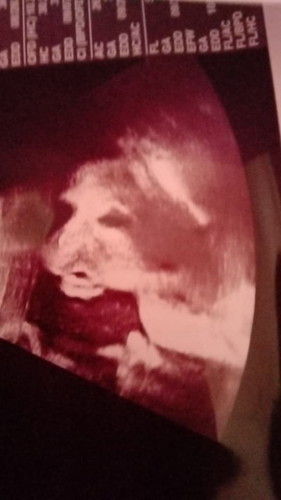

อ้าปากหว๋อเรยลูก👶🤗 #ไปอัลตราซาว์มามื้อวานนี้ครับ# กำหนดคลอด25 กันยายน 2564 🤰เเม่ๆบ้านไหนคลอดเดือนกันยายบ้างเอ่ย🥳